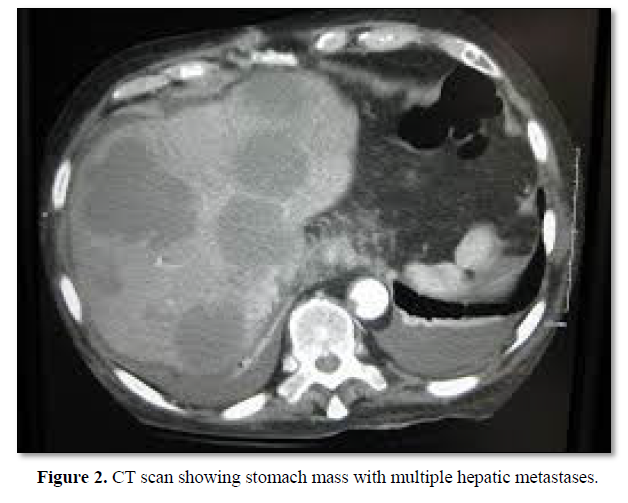

Biopsy showed SCC of stomach without any adenocarcinoma component. CT scan (Figure 2) done for metastatic workup which showed antral mass with perigastric nodes and multiple hepatic focal lesions which was in operable. Further pathological examination of the biopsy specimen revealed SCC characteristics, displaying a typical keratin pearl formation and intracellular bridges (Figure 3). Immunohistochemical staining was positive for cytokeratin as seen in Figure 4.